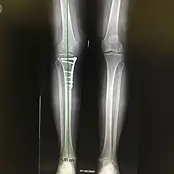

Knee Orthopedic Surgery